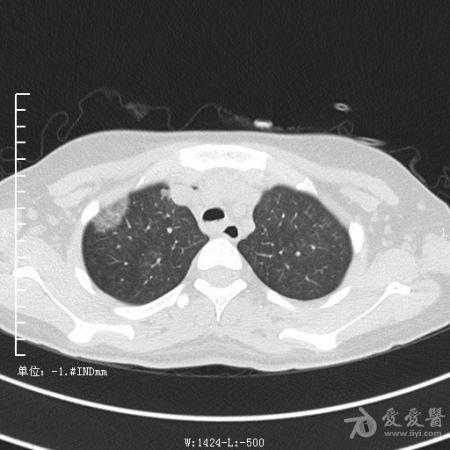

典型支气管扩张及肺水肿CT片

典型支气管扩张肺水肿